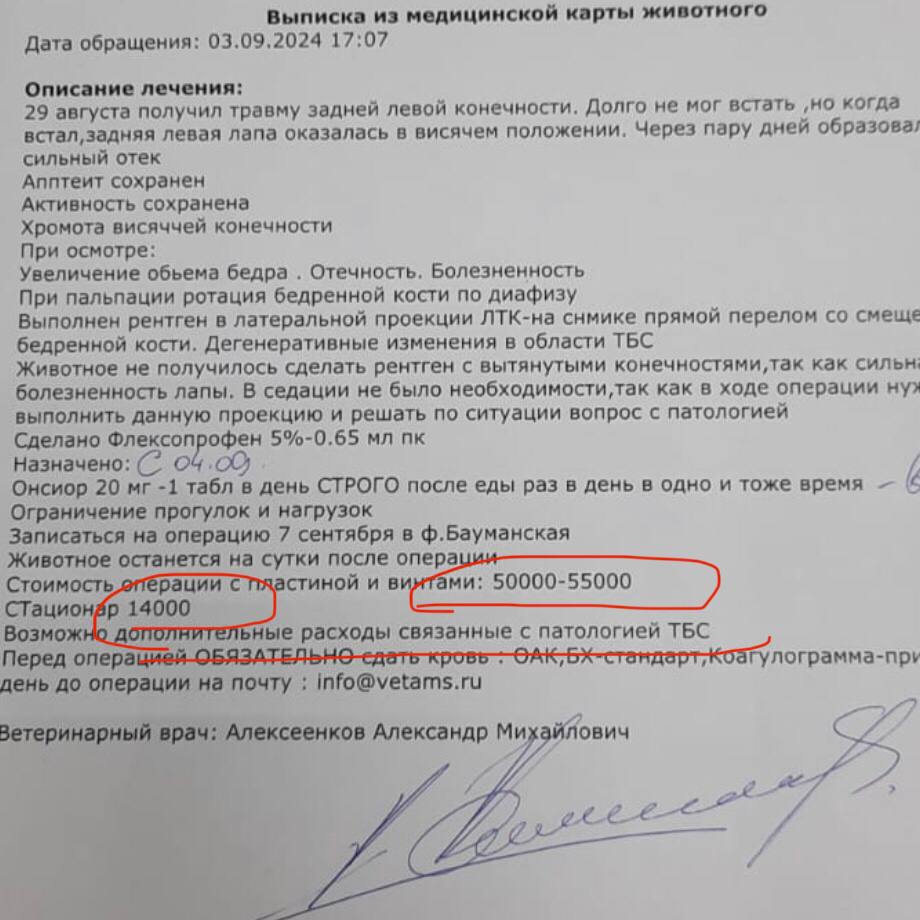

Здравствуйте,прошу откликнуться.В сентябре подобрала собачку,с поломанной лапой,сделали операцию,было смещение.Очень долго не срастался перелом.После сняли конструнцию,но около месяца назад Снова перестал становиться на лапу и сильный отек.Так как в клинике за операцию у меня все еще долг нас не примут больше,я внесла сумму 40 тысяч а долг около 20 ти еще. Предварительно нам озвучили что вероятнее всего нужно ампутировать лапу.Прошу вас кто может забрать собаку,что бы ее спасти,я не смогу сейчас осилить растраты,хоть и очень к нему привязались.Он скулит ,почти перестал кушать,я понимаю что ему больно,но не могу помочь.Прошу заберите собаку так как я не в состоянии оплатить ему лечение,выбросить на улицу не могу,усыпить подло.